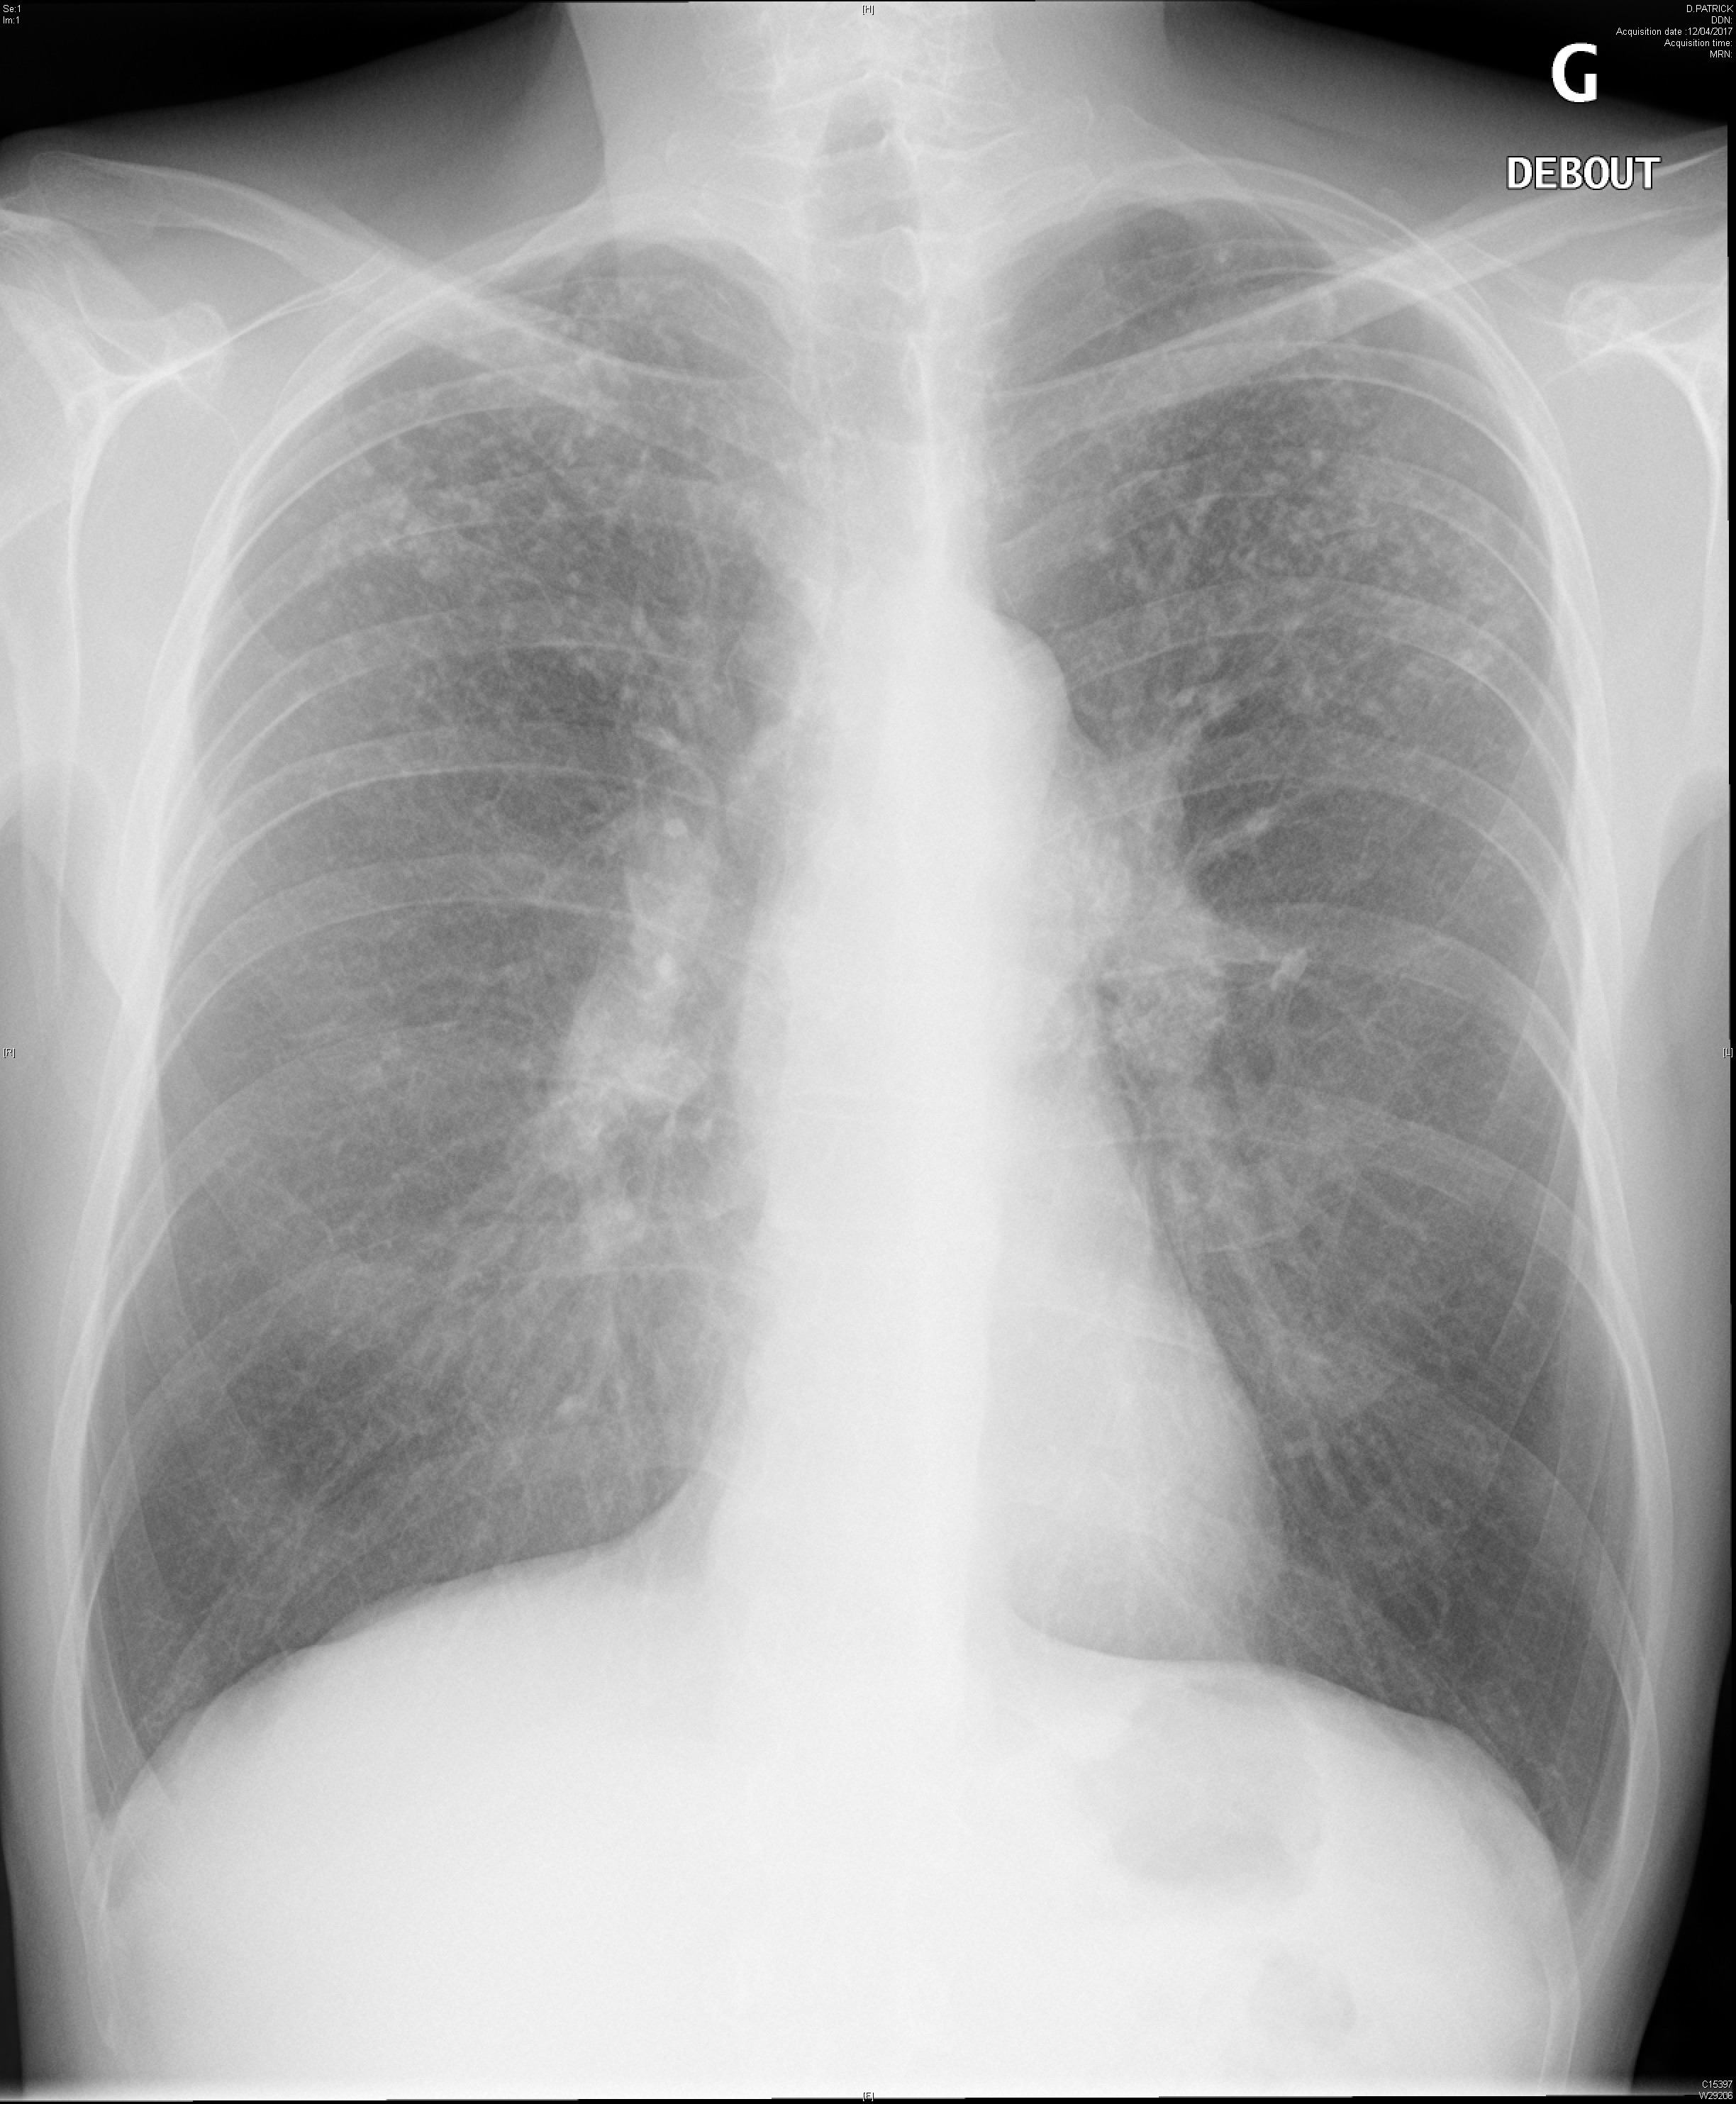

Miliaire pulmonaire dans le cadre d'une sarcoïdose

Syndrome interstitiel et adénopathies médiastinales dans le cadre d'une sarcoïdose systémique